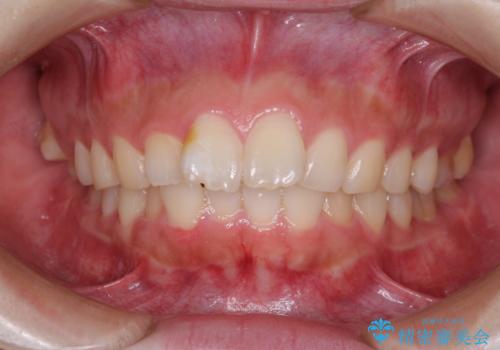

後戻りの再矯正 ワイヤー装置でデコボコと隙間を改善